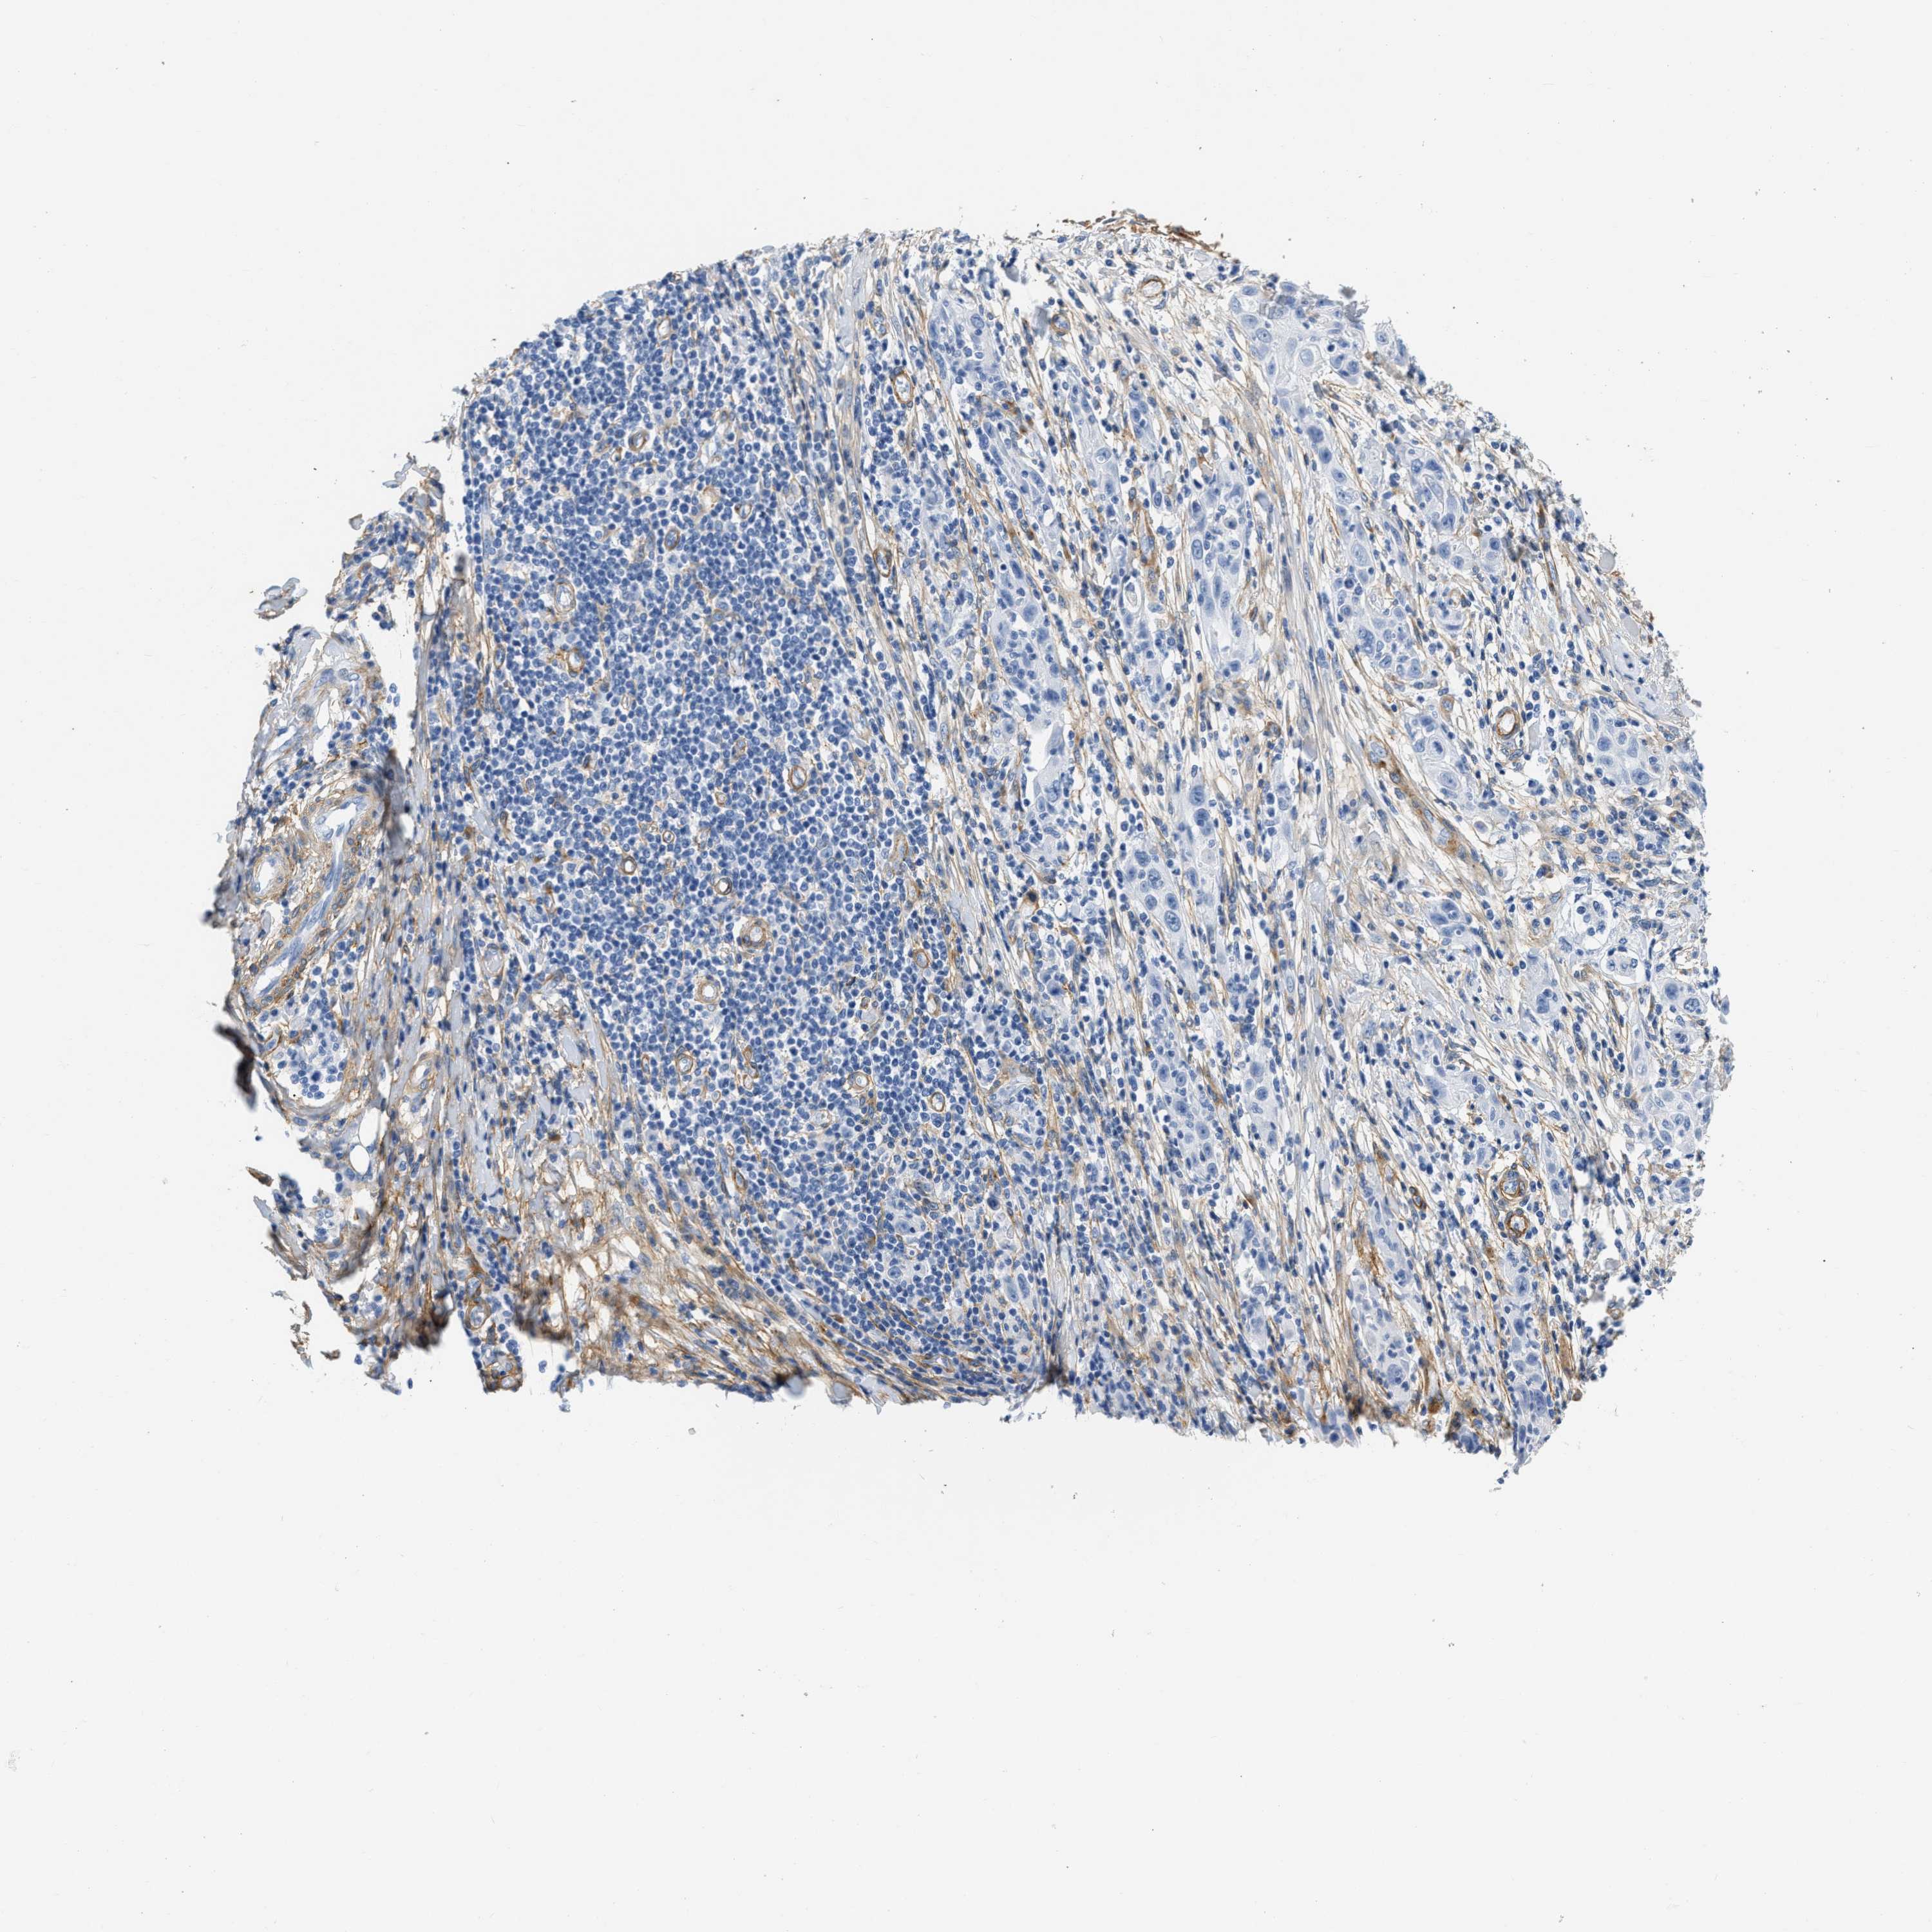

CANCER SKIN CANCER Show tissue menu

SKIN CANCER - Protein expressioni

A mouse-over function shows sample information and annotation data. Click on an image to view it in a full screen mode. Samples can be filtered based on level of antibody staining by selecting one or several of the following categories: high, medium, low and not detected. The assay and annotation is described here.

Antibody staining in the annotated cell types in the current human tissue is reported as not detected, low, medium, or high, based on conventional immunohistochemistry profiling in selected tissues. This score is based on the combination of the staining intensity and fraction of stained cells.

Each image is clickable and will lead to virtual microscopy that enables deeper exploration of all samples and also displays staining intensity scores, fraction scores and subcellular localization as well as patient and tissue information for each sample.

Antibody CAB003842

Squamous cell carcinoma, NOS

Basal cell carcinoma

Squamous cell carcinoma in situ, NOS

Squamous cell carcinoma, metastatic, NOS